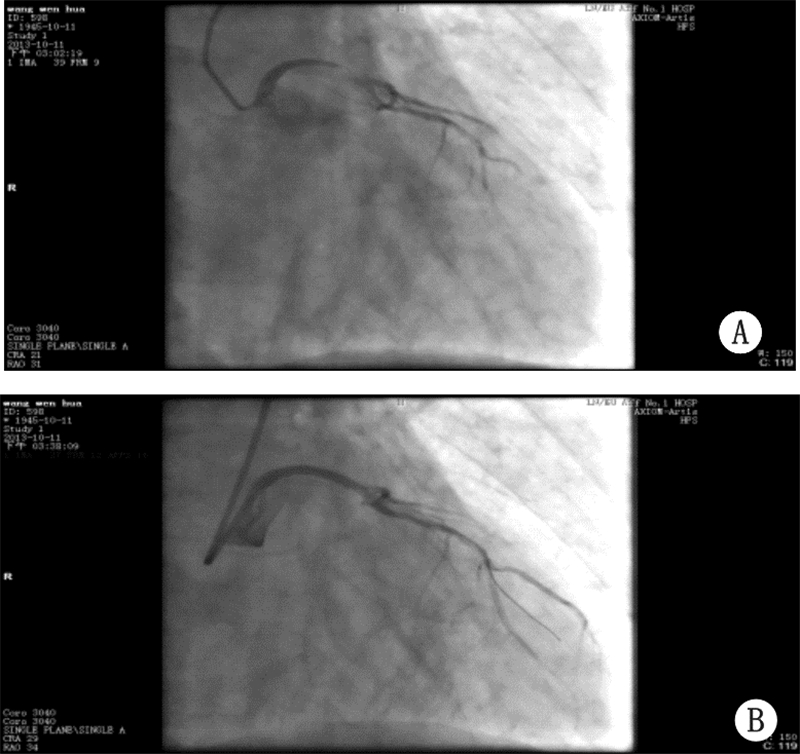

1 资料与方法患者,男,68岁,3年前无明显诱因出现阵发性烧灼样胸骨后疼痛,10~15 min/次,伴有胸闷,气短、大汗,本院诊断为“不稳定性心绞痛”,应用硝酸甘油后症状缓解。此后规律口服阿司匹林、消心痛,上述症状未再发作。入院前3 h无明显诱因出现上述症状,伴有烦躁不安、面色苍白,频繁恶心、呕吐,上腹胀痛,含服硝酸甘油上述症状未缓解。查体:P 54次/min,BP 64/47 mmHg(1 mmHg=0.133 kPa)。面色苍白、皮肤湿冷。神志清,反应迟钝。双肺呼吸音清,未闻及干湿啰音。心率:54次/min,律齐。心电图(图 1A):ST段 aVL导联上抬0.1 mV,Ⅰ、Ⅱ、Ⅲ、aVF、V4-V6导联下移0.1~0.3 mV,aVR导联上移0.2 mV。肌钙蛋白I 27.16 ng/mL。诊断:急性心肌梗死,考虑左主干病变,心源性休克。治疗:常规用药包括:肝素抗凝、可定调脂、多巴胺升压。抗血小板治疗:阿司匹林首剂量300 mg,维持量100 mg/d口服,波立维首剂量600 mg/d,维持量75 mg/d口服;术后常规应用替罗非班静点36 h。急诊冠状动脉造影:左主干末端至左前降支近段95%狭窄,见血栓影,血流TIMI 1级,左回旋支近段100%闭塞,考虑为慢性闭塞,血流TIMI 0级,右冠状动脉弥漫性病变,最窄处50%狭窄,可见侧枝循环向左回旋支供血,血流TIMI 3级(图 2A)。决定行急诊PCI:送6FEBU3.5 指引导管至左冠开口,送Runthrough导丝通过病变处到达前降支远端,再送2.0 mm×15 mm迪马克球囊至前降支至左主干病变处,以12 atm×5″由远至近进行扩张3次,造影示左主干至前降支病变处残余狭窄80%,血流TIMI 2~3级,送乐普3.5 mm×36 mm支架不能通过病变处,送BMW导丝通过病变处,再送乐普3.5 mm×36 mm支架至左主干至前降支病变处,以16 atm×5″进行扩张,释放支架,造影示支架释放满意,无夹层及残余狭窄,血流TIMI 3级(图 2B)。左回旋支病变暂不处理。结果:术后患者胸痛缓解,血压、心率恢复正常。心电图:6 h内aVL导联ST段回降,V3-6导联ST段回到基线(图 1B)。

![]() |

| 图 2 患者发病时急诊冠状动脉造影结果(A)及 左主干放置支架后造影结果(B) |